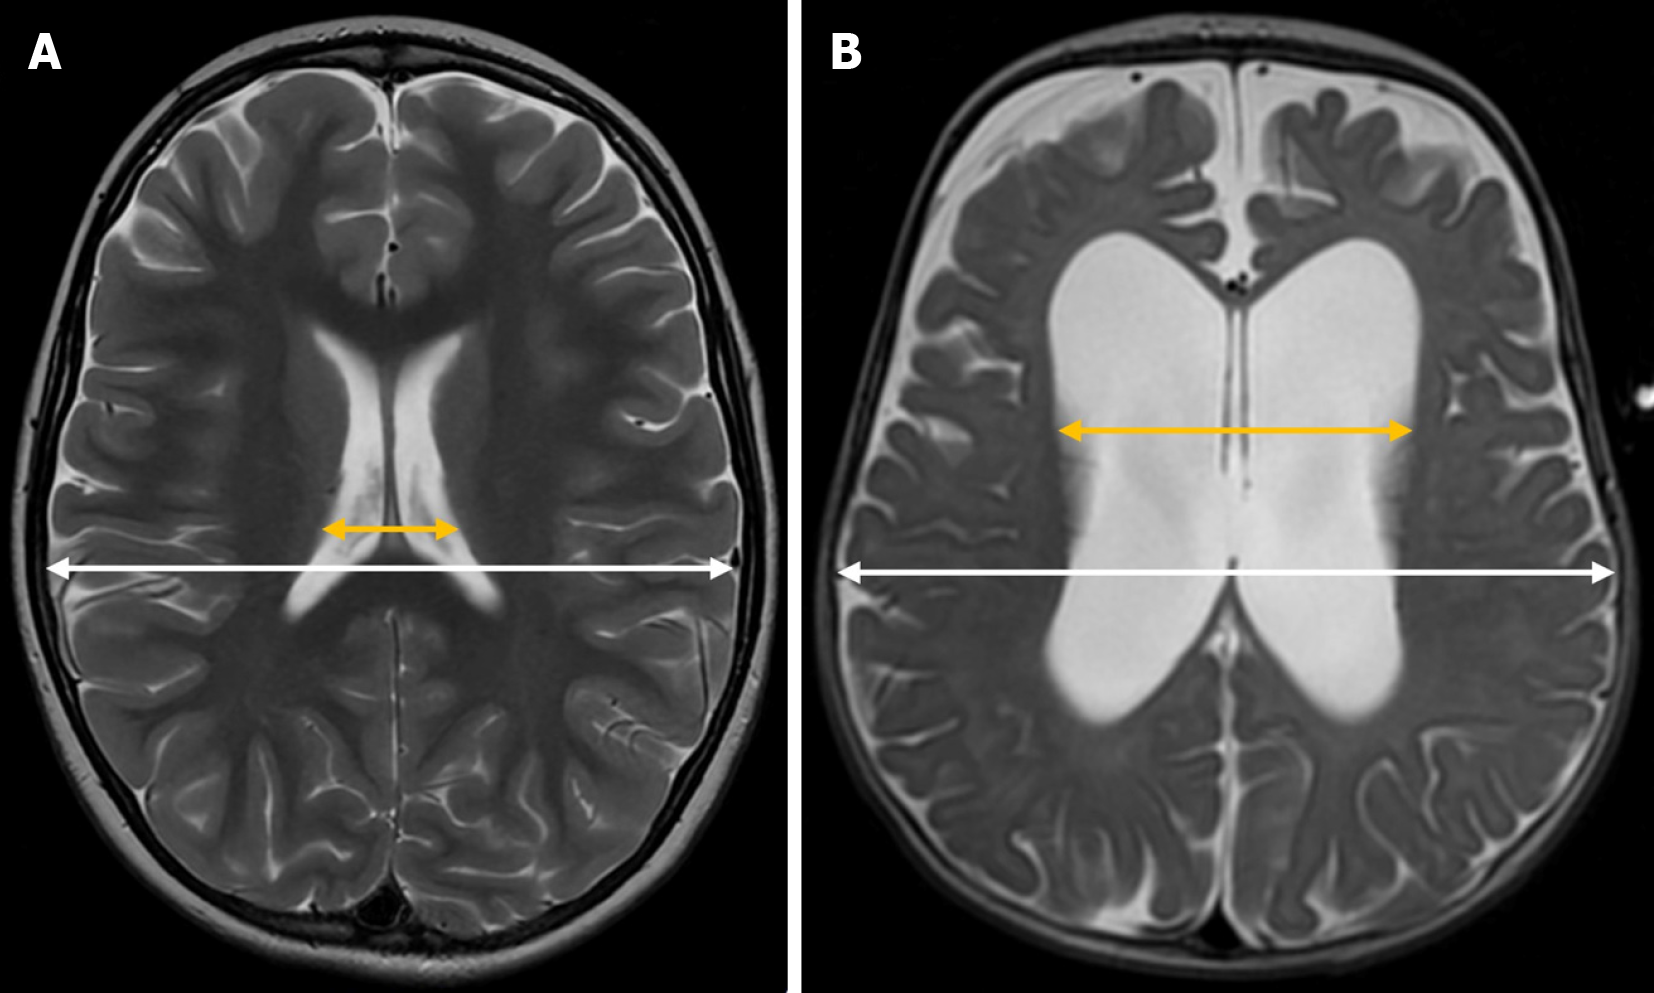

Evans’ index is a simple neuroimaging measurement used to assess the relative size of the lateral ventricles in proportion to the cranial size. It is calculated by dividing the maximum width of the frontal horns of the lateral ventricles by the maximum inner diameter of the skull in the same axial plane on brain MRI or CT scans[23] (Figure 3). In pediatric patients, it is also applied using transfontanellar ultrasound[3,24], where it is obtained from a strict coronal plane.

In adults, ventricular dilation is generally assumed when this index exceeds 0.3. However, in the pediatric population, standardized cutoff values are not well established, as they tend to vary depending on the specific population studied[25].

To calculate this index, the maximum diameter of both the frontal and occipital horns of the lateral ventricles is measured in the same axial plane at the level of the foramen of Monro. The sum of these measurements is then divided by twice the maximum intracranial biparietal diameter[31] (Figure 6).

In healthy pediatric patients, the mean FOHR is approximately 0.37, with a 95% confidence interval ranging from 0.36 to 0.38, regardless of age[31]. A value exceeding 0.44 is considered indicative of ventricular enlargement[32].